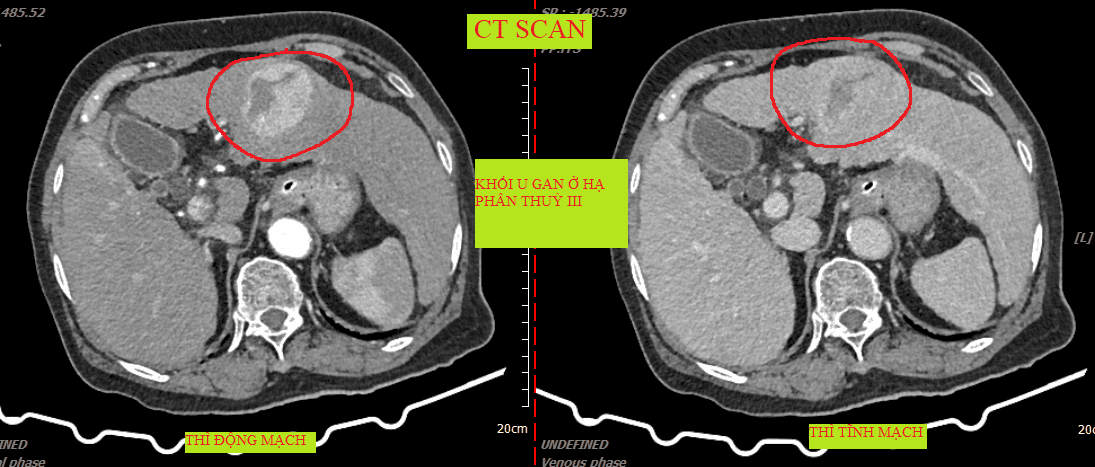

CT khối u gan.